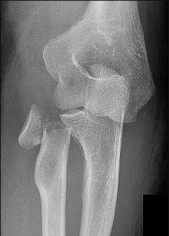

A 15-year-old male presents with deep knee pain awakening him at night. Radiographs show a permeative destructive lesion in the distal femoral metaphysis with a 'sunburst' periosteal reaction and Codman's triangle.

Biopsy confirms high-grade conventional osteosarcoma. What is the most critical prognostic factor for long-term overall survival in this patient?